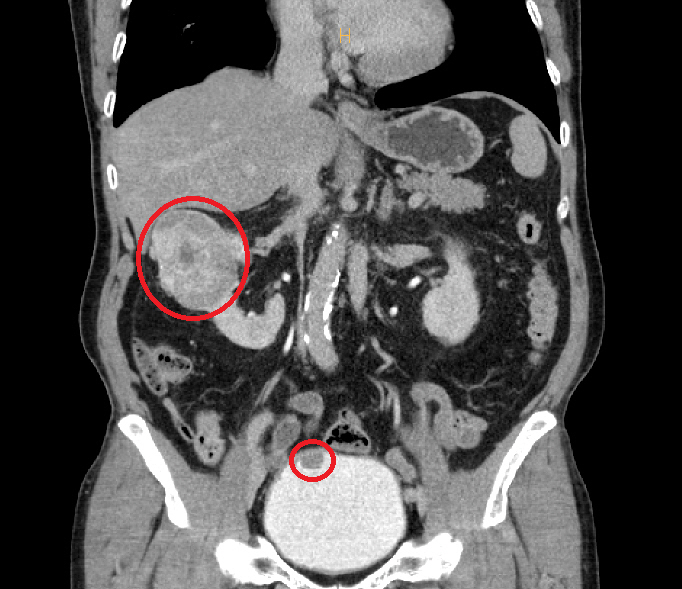

CT 검사에서 약 7㎝ 크기의 신세포암(위)과 방광암(아래)이 동시에 발견된 모습.

순천향대학교 부천병원에서 73세 환자의 7cm 신세포암을 로봇 부분절제술로 성공적으로 제거하며 신장 기능을 보존하는 혁신적인 수술이 진행됐다. 이 병원은 고난도 로봇수술 경험을 바탕으로, 일반적으로 전절제술이 필요한 크기의 종양에서도 부분절제술을 선택하여 환자의 삶의 질을 높이고 있다.

이번 수술은 신장과 방광에서 동시에 발견된 암을 다루는 복잡한 과정으로, 이상욱 교수는 '신장 기능을 지키는 것이 환자의 삶의 질에 매우 중요하다'고 강조하며 맞춤형 수술의 필요성을 역설했다. 로봇 수술을 통해 출혈을 최소화하고 정밀한 절제가 가능해져, 환자의 회복에도 긍정적인 영향을 미칠 것으로 기대된다.